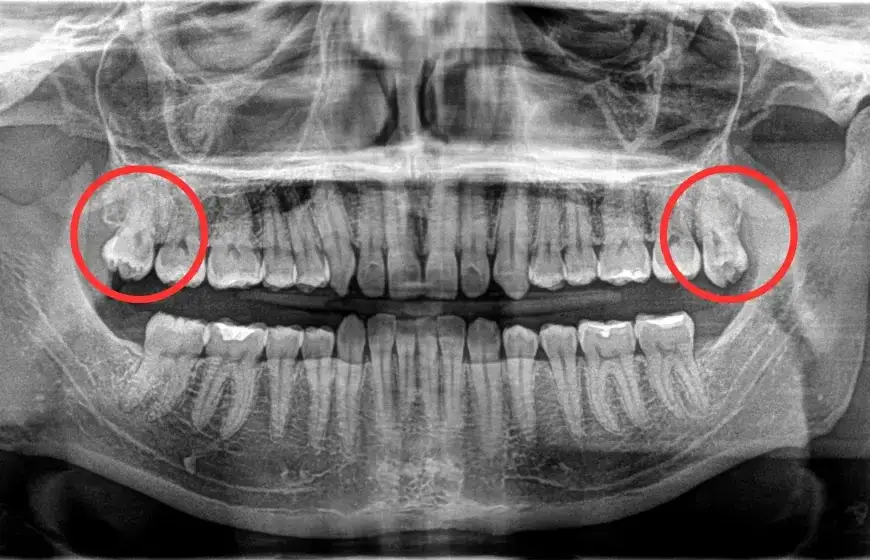

Jeśli podejrzewasz, że ząb mądrości rośnie nieprawidłowo, pierwszym krokiem powinna być konsultacja z dentystą. Specjalista może zalecić wykonanie zdjęcia RTG, które pozwoli ocenić położenie zęba i ewentualne komplikacje zębów mądrości. Inne badania to tomografia komputerowa, która dostarcza bardziej szczegółowych informacji.

- RTG panoramiczne – pokazuje położenie zęba i sąsiednich struktur.

- Tomografia komputerowa – szczegółowe obrazowanie w przypadku skomplikowanych przypadków.

- Badanie kliniczne – ocena stanu dziąseł i sąsiednich zębów.